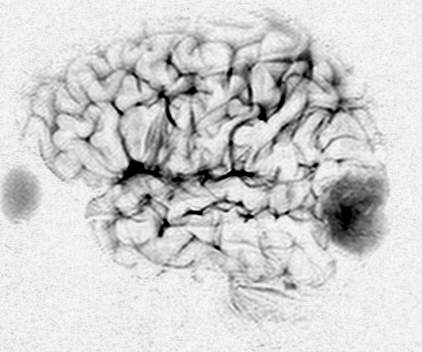

3歳で発症し自動症と診断されていた例

3歳で最初のてんかんらしいと言われる発作があり,その後は発作は見えず自動症と診断され徐々に学習能力の低下が認められ,7歳の時に外来を訪れました。週に3回くらい腹痛や嘔気があってすぐに眠くなってしまう。耳鳴がすごくてしばらく何も聞こえなくなってしまう,話も理解できなくなるなど,側頭葉てんかんの特徴をたくさんエピソードとして持っていましたが,症候性てんかんとは診断されませでした。側頭葉にどのような機能があるのかを証明してくれる症例でもあります。

典型的なDNTの画像で説明するまでもありません。ガドリニウムでは全く増強されませんでした。左上側頭回と角回の境界域に存在します。

側脳室壁のあたりまで全摘出しました。とても柔らかい腫瘍で吸引できました。